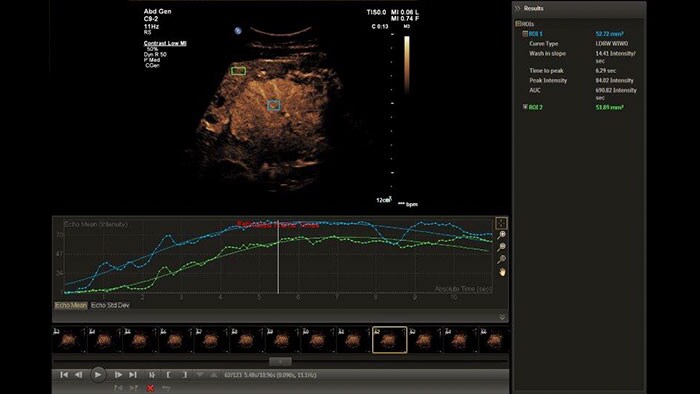

The Q-App Region of Interest (ROI) provides dedicated tools for spatial and temporal analysis of regions of interest in 2D, color and contrast enhanced* ultrasound exams (CEUS). This Q-App also provides basic 2D measurement tools (distance, area) as well. For CEUS applications, multiple motion compensated regions can be defined for contrast bubble analysis to generate wash-in/wash-out curves for lesion blood flow assessment.